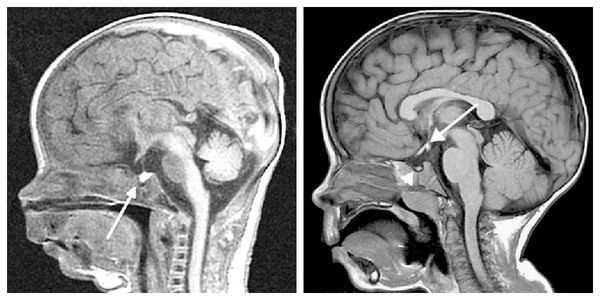

У некоторых пациентов с мутацией конкретных генов выявляется гиперплазия передней доли гипофиза (аденогипофиза). В процессе жизни может произойти её атрофия вплоть до формирования синдрома "пустого турецкого седла" — недостаточности области головного мозга, где расположен гипофиз. Данный синдром приводит к внедрению мягкой мозговой оболочки в полость турецкого седла, сдавлению и уменьшению гипофиза, что нарушает или полностью прекращает его работу.

При необходимости проводится МРТ головного мозга и гипофиза с контрастированием [6] . Она позволяет исключить или подтвердить наличие объёмных образований области гипофиза и головного мозга.

Для выяснения формы нанизма необходимо исследование инсулиноподобного фактора роста (соматомедина-С), ТТГ, ЛГ, ФСГ, Т3, Т4, кортизола в плазме и моче, антител к тиреоглобулину, микросомальной фракции тироцитов и др. Для исключения опухолевого поражения проводится КТ (МРТ) головного мозга.